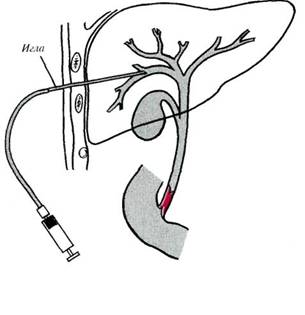

4. назовите примененный способ и опишите его

5. назовите представленные на рис. Анастомозы